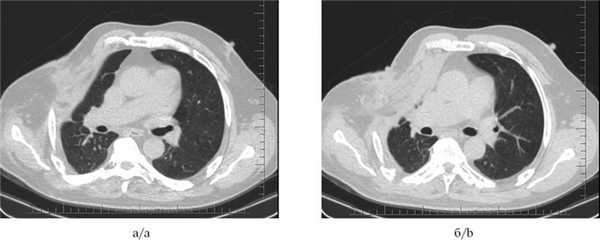

Рис. 5. Мультиспиральные компьютерные томограммы органов грудной клетки через 1 мес после установки бронхоблокатора и выполненного оперативного вмешательства (a и б): ателектаз легочной ткани; остаточная плевральная полость не определяется, торакостома ликвидирована.